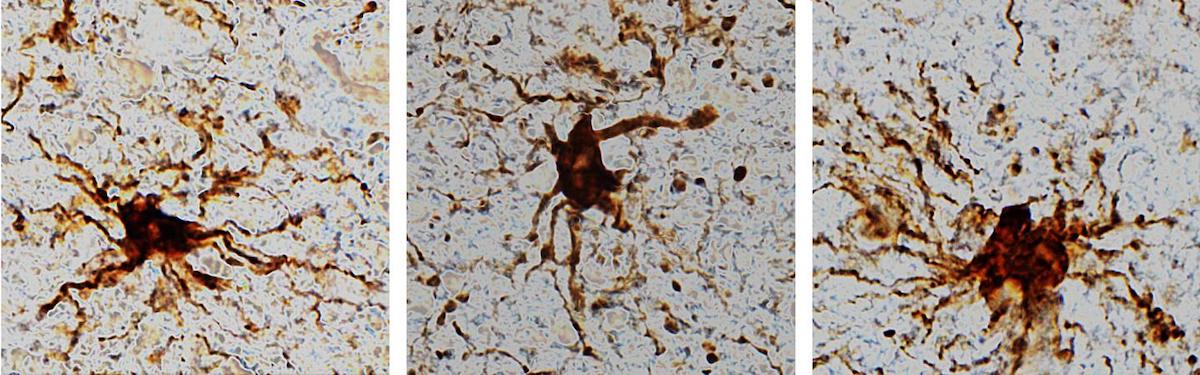

Ces "gènes zombies" comme ils les appellent, soit ceux dont l'expression augmente après l'intervalle post-mortem, étaient spécifiques à un type de cellule : les cellules gliales (des cellules inflammatoires). Les chercheurs ont observé que les cellules gliales, durant plusieurs heures après la mort, grandissent et se dotent d'appendices ressemblant à de longs bras. Les résultats ont été publiés récemment dans la revue Scientific Reports.

« Le fait que les cellules gliales s'agrandissent après la mort n'est pas très surprenant pour nous, étant donné qu'elles sont inflammatoires et que leur rôle est de nettoyer les lésions cérébrales telles que le manque d'oxygène ou celles résultant d'accidents vasculaires cérébraux », a déclaré le Dr Jeffrey Loeb, professeur et directeur du département de neurologie et de réadaptation de la faculté de médecine de l'UIC, et auteur correspondant de l'article.